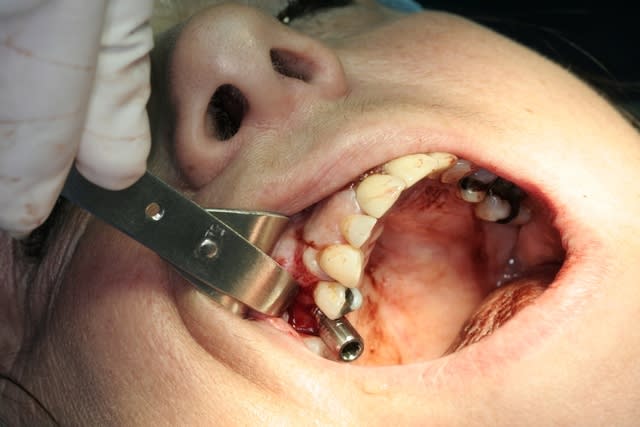

là, y avais quand même pas mal d'os...la crète, assez régulière devais bien faire 5 à 6mm...j'aurais très bien pu poser sans faire d'expansion...

mais c'est surtout la qualité osseuse qui m'a fait faire ce choix...la densité me semblait pas top (souvent le cas dans les sites avec agénésie...) et c'était l'occasion en plus d'améliorer, ou plutôt d'éliminer, la légère concavité vestibulaire...

et puis là au moins pas de problème de stab primaire...(remarques, valait mieux...pour la mise en vitrine immédiate...)...le moteur a calé (couple réglé...) à 72N/cm...et j'ai fini à la clef à cliquet directement dans l'hexagone de l'implant...je devais à mon avis être largement au delà des 100N/cm...